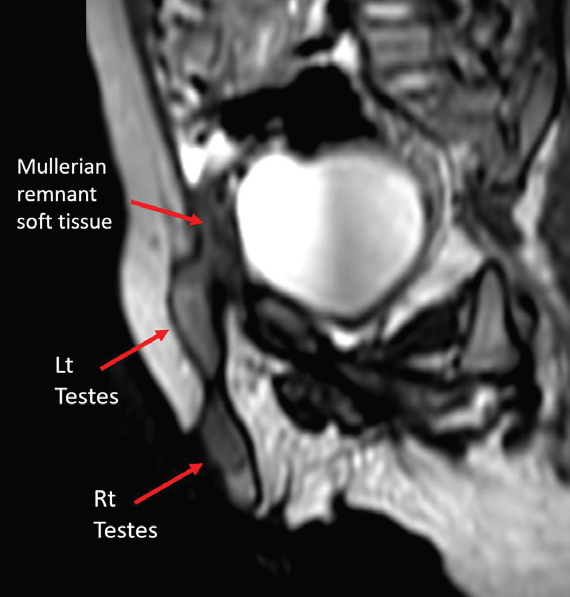

MRI pelvis was performed for soft tissue characterization. T2- weighted sequences demonstrated two testes on the right side—one within the scrotum and the other at the superficial inguinal ring. The ectopic left testis was smaller than the right testis. Additionally, an intermediate-signal-intensity structure was noted in the right inguinal canal, distinct from both testes, suggestive of a Müllerian derivative [Figure 4-6].

Figure 4: Coronal T2-weighted MRI showing bilateral testes located on the

same side of the pelvis—one in the scrotum and the other in the inguinal ring.

Figure 5: Oblique sagittal T2-weighted MRI demonstrating a soft tissue

structure in the superficial inguinal ring, different in signal intensity from the

testes, suspicious for Müllerian remnant.